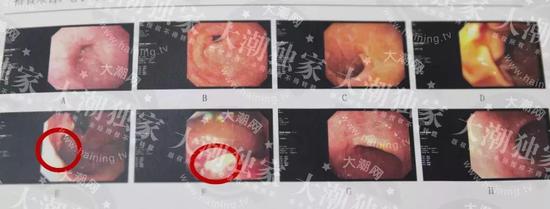

△紅圈圈出位置為癌變部位 △紅圈圈出位置為癌變部位